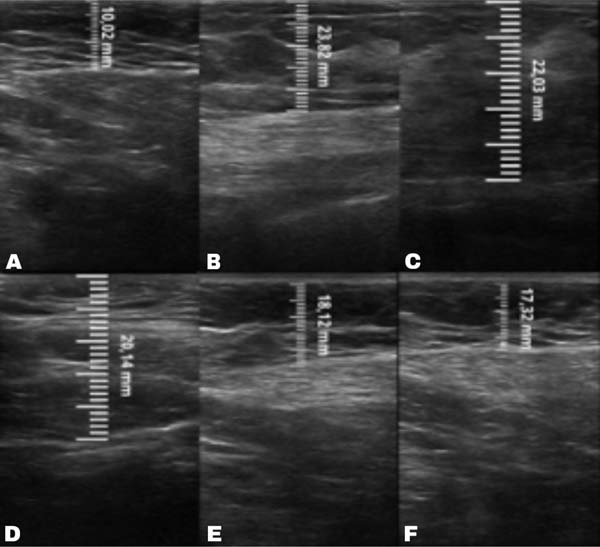

A mensuração da espessura do tecido subcutâneo é realizada de forma vertical, do ponto mais alto (logo na transição da epiderme) ao ponto mais baixo (na transição com o tecido muscular) da espessura de tecido subcutâneo. Essa medida é de fácil reprodutibilidade para quem possui aptidões básicas em ultrassonografia. ►Fig. 2. A medida da espessura de tecido subcutaneo na mama lipoenxertada foi realizada no pré- e pós-operatório imediato da lipoenxertia, e após 15,30, 90 e 180 dias. As medidas foram feitas atraves da ultrassonografia, em milimetros, medindo a distancia vertical do ponto mais superior (proximo à epiderme) ao mais inferior (proximo à musculatura adjacente) do tecido subcuta neo no ponto previamente definido. Foi utilizado equipamento de ultrassom modelo GE, LOGIQP6 (GE Healthcare) com uso de sonda linear de 11L com faixa de frequencia de 12 a 6 MHz, operado por cirurgião com pós graduação lato sensu em ultrassonografia geral. ►Fig. 3.

No grupo enxerto decantado, a reducãomédia, comparando-se a espessura inicial apos lipoenxertia, foi de 9,90% no 15° dia, 19,27% no 1° mes, 23,59% no 3° mes e 26,36% no 6° mes. No grupo enxerto filtrado, a reducao media, comparando-se a espessura inicial apos lipoenxertia, foi de 7,74% no 15° dia, 14,85% no 1° mes, 20,67% no 3° mes e 22,80% no 6° mes. ►Fig. 6. A evolução ao ultrassom da espessura do tecido subcutâneo antes e depois da lipoenxertia pode ser vista nas ►Figs. 7-8. Os resultados de pré-e pós-operatório de uma paciente de cada um dos grupos estão exibidos nas ►Figs. 9-10.